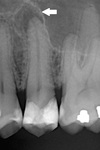

Apical radiolucency with sinus tract marker leading to apex – diagnosis?

A

• Periodontitis periapicalis chronica cum fistula

• (chronic apical periodontitis with fistula).

• Treatment: RCT or extraction

* Periodontitis periapicalis chronica cum fistula * (Chronic apical periodontitis with fistula) → Gutta-percha point tracing to apex